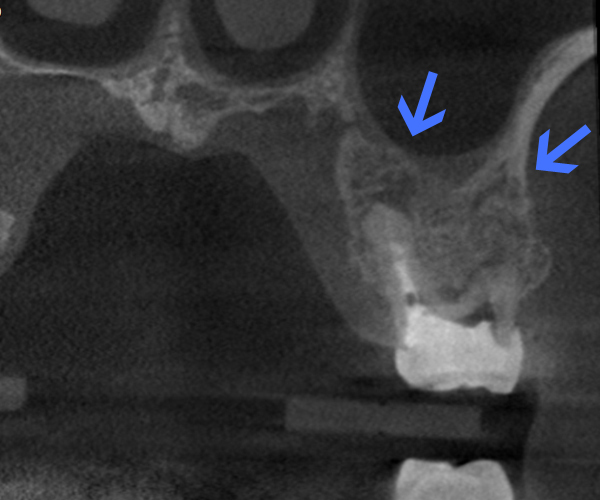

Before

歯性上顎洞炎(副鼻腔炎)

根尖病巣により洞底膜がラッパ状に開いている。

After

6ヶ月後のCT

洞底膜はきれいに再生され病巣は消失しております。